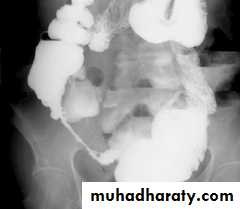

Multiple dilated small bowel loops are present. The valvulae conniventes

are thin and straight and closely stacked together.

A. Dilatation: > 30 mm. The folds are effaced & the valvulae conniventes become clearly visible.1. Malabsorption.